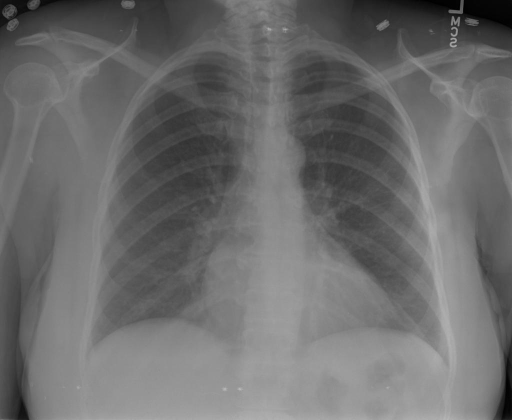

# 本文贡献  - 借助ChatGPT以及公开的数据集,我们构造了一个`X光影像-诊断报告`对的医学多模态数据集; # 数据集 - [MIMIC-CXR](https://physionet.org/content/mimic-cxr-jpg/2.0.0/)是一个公开可用的胸部X光片数据集,包括377,110张图像和227,827个相关报告。 - [OpenI](https://openi.nlm.nih.gov/faq#collection)是一个来自印第安纳大学医院的胸部X光片数据集,包括6,459张图像和3,955个报告。 在上述工作中,报告信息都为非结构化的,不利于科学研究。为了生成合理的医学报告,我们对两个数据集进行了预处理,并最终得到了可以用于训练的**英文报告**。除此之外,为了更好的支持中文社区发展,借助ChatGPT的能力,我们将英文报告进行了中文翻译,并最终形成了可用于训练的数据集。 |数据集|数量|下载链接| |:-|:-|:-| |MIMIC-CXR-zh|-|-| |OpenI-zh|6,423|[诊疗报告](./data/Xray/openi-zh.json) 、[X光影像](https://pan.baidu.com/s/13GBsDMKf6xBZBSHpoWH_EA?pwd=k9sh)| # 快速上手 1. 安装环境 ```bash # 安装依赖 pip install -r requirements.txt # 国内换源安装依赖 pip install -i https://mirrors.aliyun.com/pypi/simple/ -r requirements.txt ``` 此时默认会安装`deepspeed`库(支持`sat`库训练),此库对于模型推理并非必要,同时部分`Windows`环境安装此库时会遇到问题。 如果想绕过`deepspeed`安装,我们可以将命令改为: ```bash # 安装依赖 pip install -i https://mirrors.aliyun.com/pypi/simple/ -r requirements_wo_ds.txt # 安装SwissArmyTransformer pip install -i https://mirrors.aliyun.com/pypi/simple/ --no-deps "SwissArmyTransformer>=0.3.6" ``` 2. 模型推理 CLI推理: ```python python cli_demo.py --from_pretrained checkpoints/finetune-XrayGLM-05-25-01-04 --prompt_zh '详细描述这张胸部X光片的诊断结果' ``` 更多[参数](https://github.com/WangRongsheng/XrayGLM/blob/main/cli_demo.py#L16) # 效果展示 诊断: |X光影像|诊疗报告(医生)|XrayGLM| |:-|:-|:-| ||根据X射线图像,心脏大小正常,肺部看起来很清晰。已经排除了肺炎、积液、水肿、气胸、腺病、结节或肿块的存在。该发现表明一切正常。换句话说,总体印象是胸部正常。|X光片显示,心脏大小正常。肺部没有气胸或胸腔积液的证据。骨骼结构看起来没有任何异常。总的来说,X光片表明没有发现急性心肺疾病的迹象。| ||X光图片显示没有扭曲的区域、可疑的骨质不透明度或胸腺积液。心脏大小轻微增大,但非常稳定。此外,没有气胸的证据,肺野也正常。总体来说,X光片显示没有急性心脏异常,但要注意轻微的心脏扩大。|X光片显示,心脏大小正常。肺部和纵隔轮廓清晰,没有气胸或胸腔积液的证据。骨骼结构完整,没有任何急性异常。| ||心影形态在正常范围内。没有急性骨质异常。有可能出现没有明显的吸水或肺实质状况的线索。没有大面积积液或气胸。有可能怀疑其有误吸或肺实质问题。为了确诊和治疗,可能需要进行适当的影像学随访。|心脏大小正常,肺部和纵隔轮廓清晰。没有急性异常或活动受限的证据。没有任何明显的气胸、胸腔积液或肺不张的迹象。此外,也没有发现任何局灶性骨质异常或其他急性疾病。| 多轮对话: |X光影像|诊疗报告(医生)| |:-|:-| ||右侧主动脉突出观察到。心脏大小正常。胸部未发现明显的肺气肿、胸膜积液或可疑的肺部病变。报告指出已知右侧主动脉情况正常。| ```bash >> X光影像路径:./data/Xray/861_1.png >> 用户:这是一张什么图? >> XrayGLM:这张图片显示的是一张肺部检查的X光片。 >> 用户:请描述这张胸部X光片的诊断结果 >> XrayGLM:心脏大小正常,肺部清晰。没有急性心肺疾病的证据。 >> 用户:是否存在肺气肿? >> XrayGLM:没有肺气肿。心脏大小正常,肺部清晰。没有发现急性心肺疾病的证据。 >> 用户:平时饮食该注意什么? >> XrayGLM:饮食应该健康,均衡。建议增加蛋白质的摄入量,因为蛋白质有助于维持肌肉和骨骼的健康。多食用蔬菜、水果、全谷物以及健康的脂肪来源如橄榄油、鱼类等可以帮助获得足够的维生素和矿物质。此外,避免过度饮酒或吸烟,这些习惯可能会对心脏健康产生负面影响。 ``` # 项目致谢 1. [VisualGLM-6B](https://github.com/THUDM/VisualGLM-6B)为我们提供了基础的代码参考和实现; 2. [MiniGPT-4](https://github.com/Vision-CAIR/MiniGPT-4)为我们这个项目提供了研发思路; 3. ChatGPT生成了高质量的中文版X光检查报告以支持XrayGLM训练; 4. [gpt_academic](https://github.com/binary-husky/gpt_academic)为文档翻译提供了多线程加速; 5. [MedCLIP](https://github.com/RyanWangZf/MedCLIP) 、[BLIP2](https://huggingface.co/docs/transformers/main/model_doc/blip-2) 、[XrayGPT](https://github.com/mbzuai-oryx/XrayGPT) 等工作也有重大的参考意义;  这项工作由[澳门理工大学应用科学学院](https://www.mpu.edu.mo/esca/zh/index.php)硕士生[王荣胜](https://github.com/WangRongsheng) 、[段耀菲](https://github.com/IsBaSO4) 、[李俊蓉](https://github.com/lijunrong0815)完成,同时这项工作受到[檀韬](https://scholar.google.com/citations?hl=zh-CN&user=lLg3WRkAAAAJ)副教授、[彭祥佑](http://www.patrickpang.net/)老师的帮助支持。 *特别鸣谢:[USTC-PhD Yongle Luo](https://github.com/kaixindelele) 提供了有3000美金的OpenAI账号,帮助我们完成大量的X光报告翻译工作 # 免责声明 本项目相关资源仅供学术研究之用,严禁用于商业用途。使用涉及第三方代码的部分时,请严格遵循相应的开源协议。模型生成的内容受模型计算、随机性和量化精度损失等因素影响,本项目无法对其准确性作出保证。即使本项目模型输出符合医学事实,也不能被用作实际医学诊断的依据。对于模型输出的任何内容,本项目不承担任何法律责任,亦不对因使用相关资源和输出结果而可能产生的任何损失承担责任。 # 项目引用 如果你使用了本项目的模型,数据或者代码,请声明引用: ```bash @misc{wang2023XrayGLM, title={XrayGLM: The first Chinese Medical Multimodal Model that Chest Radiographs Summarization}, author={Rongsheng Wang, Yaofei Duan, Junrong Li, Patrick Pang and Tao Tan}, year={2023}, publisher = {GitHub}, journal = {GitHub repository}, howpublished = {\url{https://github.com/WangRongsheng/XrayGLM}}, } ``` # 使用许可 此存储库遵循[CC BY-NC-SA](https://creativecommons.org/licenses/by-nc-sa/4.0/) ,请参阅许可条款。